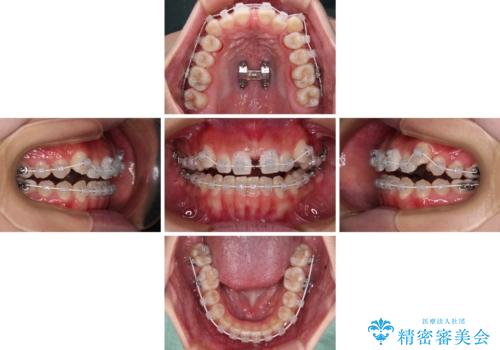

【モニター】上顎が狭い 急速拡大装置を用いたデコボコの解消

- 前歯の開咬と、上顎前歯の八重歯やデコボコを気にして来院された患者様です。

上顎歯列が狭窄していたため、急速拡大装置により上顎骨を側方に拡大し、その後ワイヤー装置にて矯正治療を行うこととしました。

上顎骨を拡大することで、八重歯やデコボコを歯列に収めることができ、下顎の歯が外に位置していた奥歯の咬み合わせも改善することができました。

スペースも短期間に獲得できるため、1年程度で治療を終えることができました。